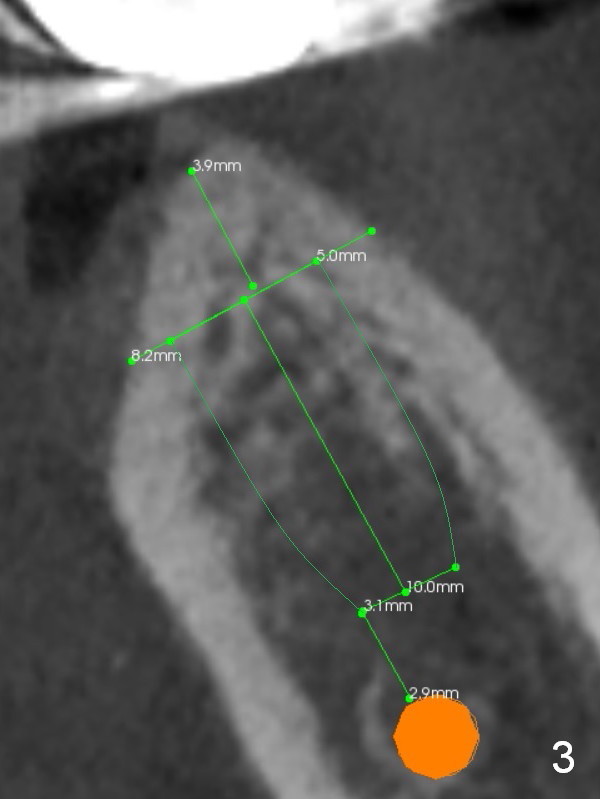

The 3-unit bridge (#18-20 in Fig.1) will be sectioned (Fig.2 red lines) with the pontic of #19 to be removed. The ridge top is narrow (Fig.3). To place a 5 mm UF implant, the triangular ridge top should be reduced (result).